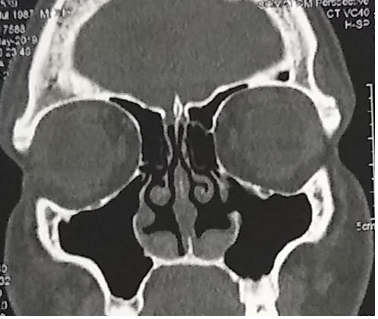

After shaped, the graft is inserted behind the pyriform aperture. Figure 3, 4, 5.

Figure 3 Close of operative view of implants placed along the lateral nasal wall just behind the piriform aperture and under the periosteum of the nasal mucosa.

Figure 4 Operative view of implants placed along the lateral nasal wall bilateral just behind the piriform aperture and under the periosteum of the nasal mucosa.

Figure 5 CT control pos surgery showing the graft inserted at the inferior and lateral nasal wall.